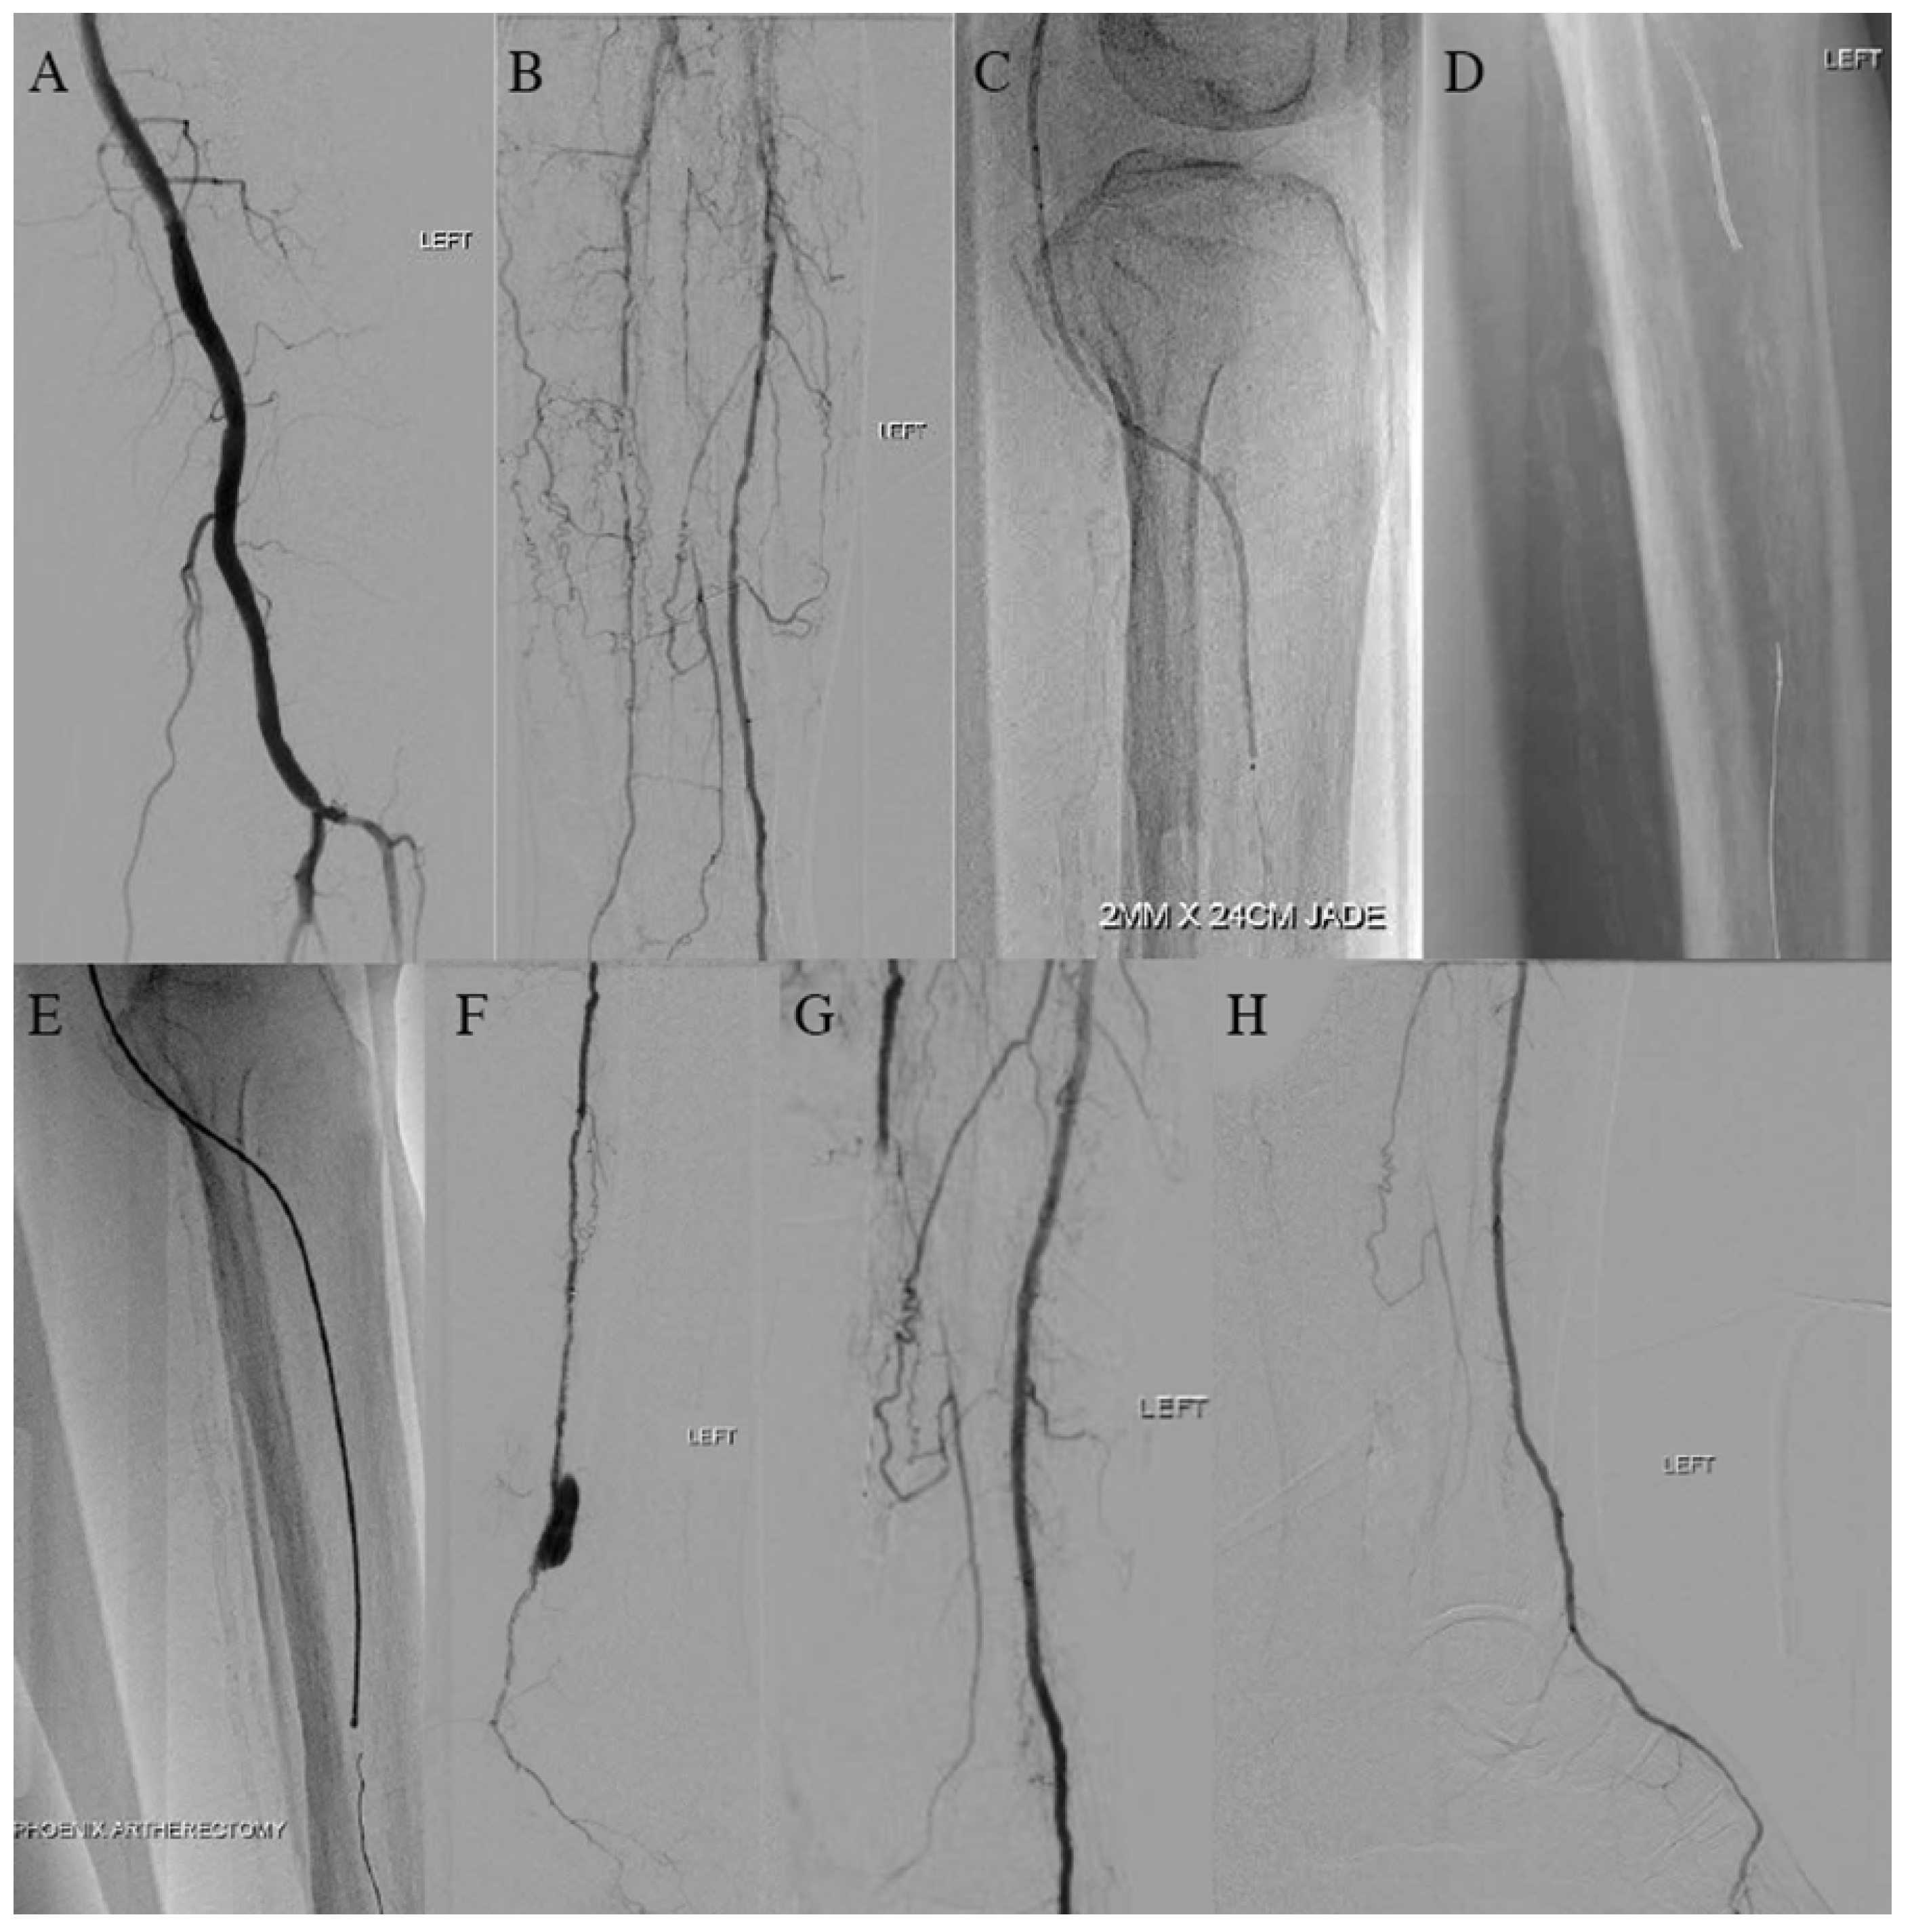

2.1. Case 1—Rotational Atherectomy for Severely Calcified Below-the-Knee (BTK) Steno-Occlusion with Chronic Limb-Threatening Ischemia (CLTI)